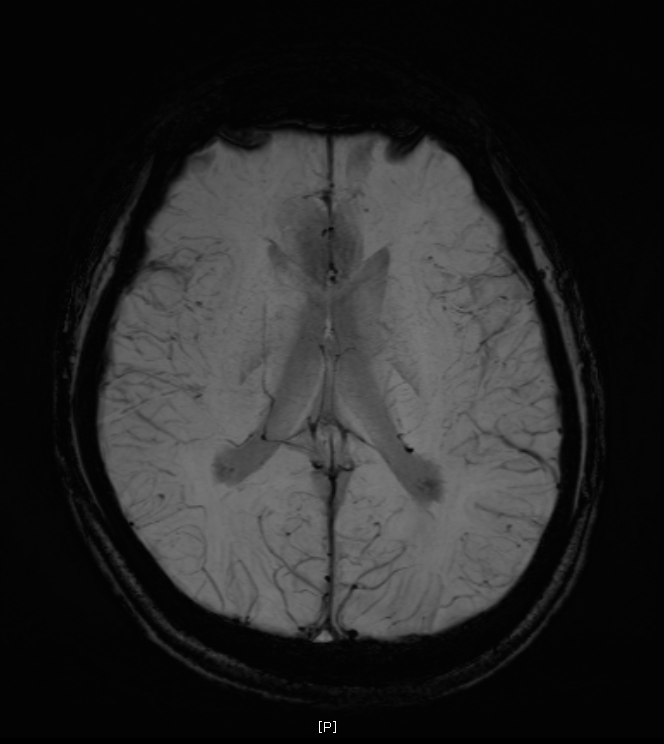

지난 금요일에 MRI를 촬영했는데요

혈관같기도 하고 하얀색 붕붕 뜨는 게 있어보이는데 (혈관같음)

한번 봐주실수 있나요? 그리고 전체적으로 괜찮은지도 봐주시면 감사하겠습니다.

특별하게 눈에 띄는 병변은 있어보이지 않습니다

말씀하신 것은 혈관의 가능성이 높겠습니다